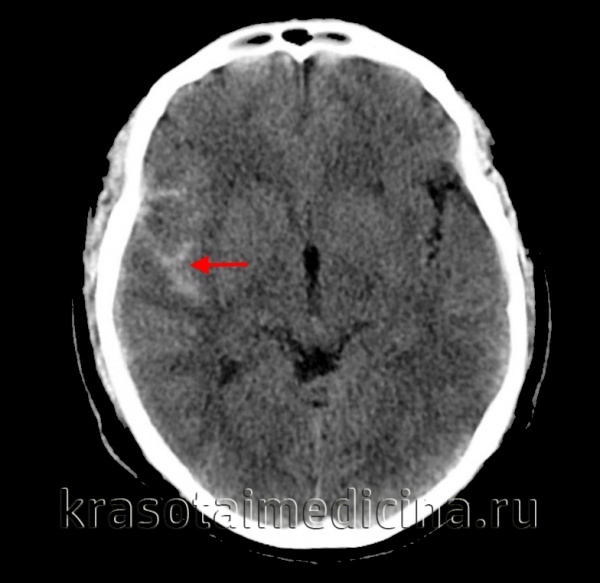

(а) Сигнал от неизмененной СМЖ подавляется на FLAIR. MPT, FAIR, аксиальный срез: у этого же пациента определяется аномальная гиперинтенсивность СМЖ супраселлярной цистерны. Гиперинтенсивный сигнал от ликвора также отмечается в области перимезенцефальных цистерн слева, верхней мозжечковой цистерны, а также теменно-затылочных субарахноидальных пространств.

(б) Бесконтрастная КТ, аксиальный срез: у мужчины 83 лет, найденного лежащим на полу, определяется диффузное САК, визуализируемое как гиперденсная жидкость практически во всех бороздах на данном снимке Также в боковых желудочках отмечается наличие границ раздела СМЖ-кровь.

(а) MPT, Т1-ВИ, сагиттальный срез: типичные признаки острого аневризматического САК. Обратите внимание на «грязную» СМЖ, изоинтенсивную по отношению к соседней мозговой ткани. Зона нормальной потери сигнала за счет эффекта потока от основной артерии окружена САК.

(б) MPT, Т1 -ВИ, аксиальный срез: у этого же пациента отмечается хороший контраст между изоинтенсивным (по отношению к мозговой ткани) «грязным» ликвором ЕЯ и внешне нормальной гипоинтенсивной («темной») СМЖ в цистернах и височных рогах боковых желудочков. (а) МРТ, выполненная через два дня после предыдущего исследования, FAIR, аксиальный срез: у того же пациента определяется диффузное распределение гиперинтенсивной жидкости в бороздах полушарий головного мозга. Также на фоне нормального подавления сигнала от ликвора в боковых желудочках отмечается наличие границ раздела кровь-ликвор.

(б) MPT, GRE, аксиальный срез: у этого же пациента в бороздах определяется скопление крови, визуализируемое как гипоинтенсивные участки «выцветания» изображения. Также в боковых желудочках хорошо видны границы раздела кровь-СМЖ.